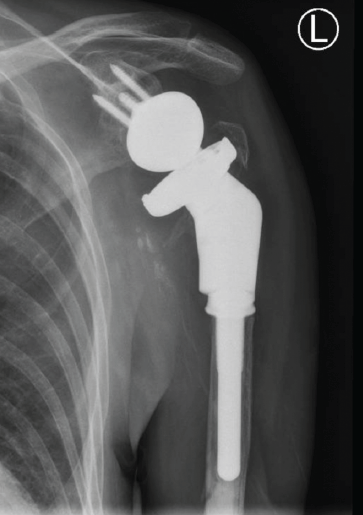

The second stage of the revision was performed 4 months after the antibiotic spacer was placed. Tissue at the time of the revision surgery revealed no white blood cells per high-powered field, so further reconstruction was performed with a custom tumor prosthesis (Comprehensive Segmental Revision System; Zimmer Biomet), which was cemented in the humeral shaft (Fig. 4).

Figure 4: Anteroposterior radiograph showing second stage of revision of reverse total shoulder arthroplasty with removal of the spacer and implantation of a tumor prosthesis.